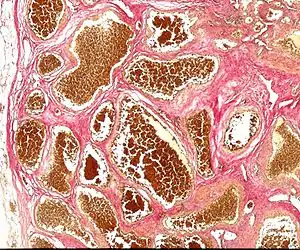

Cerebral cavernous malformation (CCM) is a cavernous hemangioma that arises in the central nervous system. It can be considered to be a variant of hemangioma, and is characterized by grossly large dilated blood vessels and large vascular channels, less well circumscribed, and more involved with deep structures, with a single layer of endothelium and an absence of neuronal tissue within the lesions. These thinly walled vessels resemble sinusoidal cavities filled with stagnant blood. Blood vessels in patients with cerebral cavernous malformations (CCM) can range from a few millimeters to several centimeters in diameter. Most lesions occur in the brain, but any organ may be involved.[1]

| Histology of a cavernous hemangioma | |